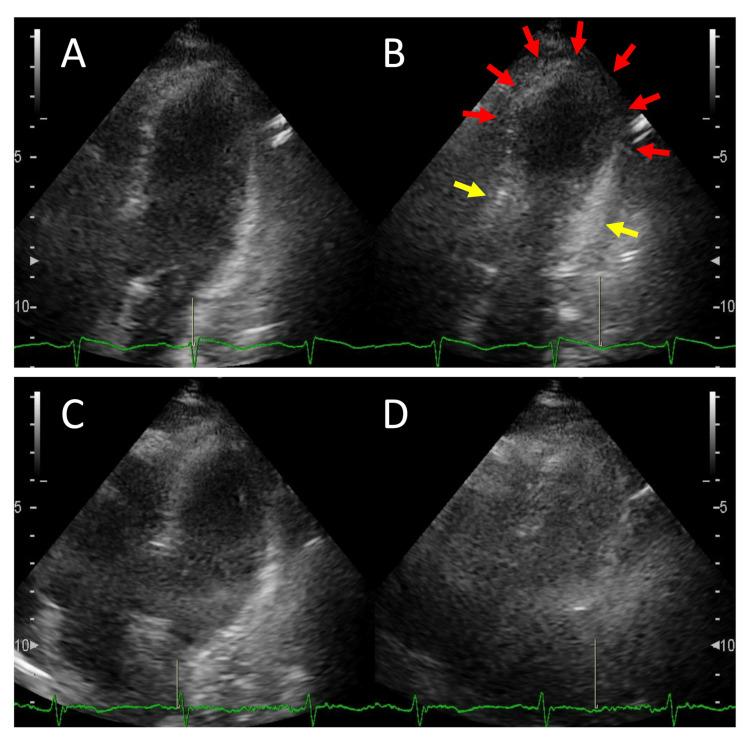

癫痫持续状态(SE)诱发的应激性心肌病(TTC)常表现为血流动力学障碍,包括休克,即便进行了心力衰竭治疗。这可能导致危及生命的事件,带来重大的诊断挑战。我们报告一例57岁女性病例,该患者成功诊断为TTC,未出现血流动力学障碍并接受了治疗。在TTC发病前两年,患者因复发性食管裂孔疝导致胃食管反流病(GERD)加重,并伴有心电图(ECG)改变。在TTC发病当天,患者出现了SE,同时因肺炎出现高热。地西泮使SE得到缓解,患者接受了针对肺炎的液体治疗和抗生素治疗。高肌酸激酶(CK)和N末端脑钠肽前体(NT-pro BNP)水平,以及心电图表现(左胸前导联ST段抬高)、经胸超声心动图表现(典型的心尖部气球样改变)和冠状动脉计算机断层扫描血管造影表现(无罪犯血管区域),证实了TTC的诊断。尽管在第14天观察到短暂的轻度左心室流出道狭窄,但在第21天消失。在疾病过程中,患者接受了保守治疗,进行了仔细的监测和随访影像学检查,未观察到休克、低血压或心力衰竭等血流动力学障碍的迹象。该病情由GERD加重后的SE和肺炎引发。极高的NT-pro BNP水平表明CK升高是由于心肌损伤而非SE,有助于早期诊断。当患者在GERD加重后出现SE和肺炎且NT-pro BNP显著升高时,应考虑TTC的诊断。